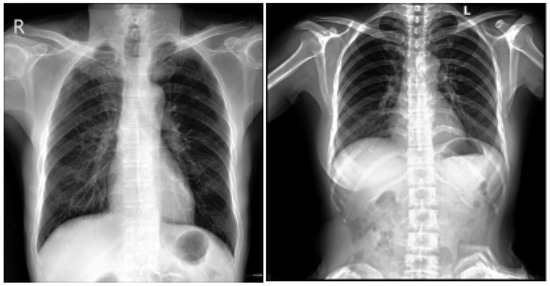

3.1.4. PadChest Dataset

This is a comprehensive and valuable resource for medical imaging research, consisting of over 160,000 CXR images obtained from 67,000 patients [28,29]. The samples from the PadChest dataset are shown in Figure 6. These images were collected between 2009 and 2017 at San Juan Hospital in Spain, representing various cases and clinical scenarios [30]. The dataset includes images captured in six position views, providing versatility for various radiological studies. Additionally, it contains extensive metadata detailing information about image acquisition techniques and patient demographic characteristics, further enhancing its utility for diverse research applications.

Figure 6.

PadChest dataset samples [28].